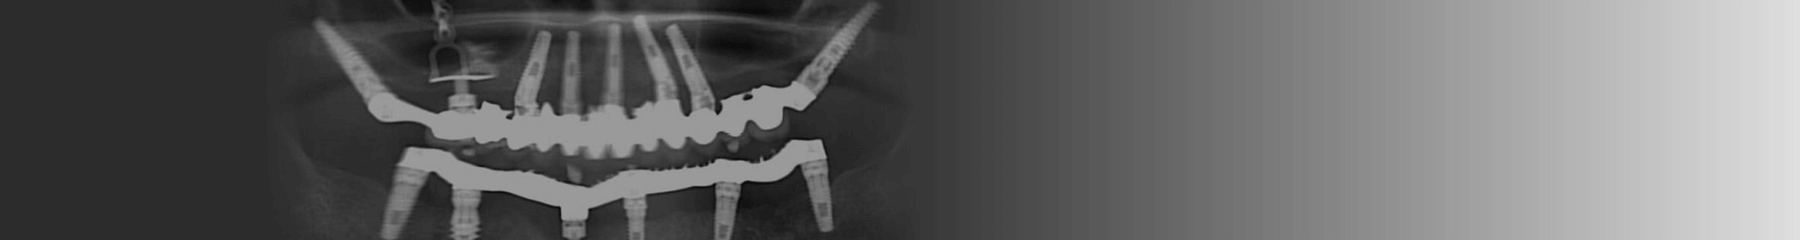

בתוכנית המומחים ששודרה ברדיו חיפה סקר ד"ר יגאל בלן, מבכירי הרופאים בישראל בתחום השתלות השיניים את ההבדלים בין טכניקות שונות להשתלות, את האתגרים שניצבים בפני רופאי השיניים במהלך הטיפול ואת הפתרונות שרפואת השיניים המודרנית מצאה לאתגרים הללו.

בין השאר הוא סקר אתגרים כמו גיל מבוגר או חוסר של עצם הלסת והשפעה שלהם על היכולת להשתיל שיניים ולשקם את הפה.

השתלת שיניים קדמיות דורשת תכנון אסתטי מוקפד ושמירה על מראה טבעי, בעוד שהשתלה של שיניים אחוריות מתמקדת בעמידות, יציבות ותפקוד לעיסה אופטימלי. לכל אזור בפה יש אתגרי השתלה משלו, ולכן נדרש תכנון אישי בהתאם למצב המטופל.